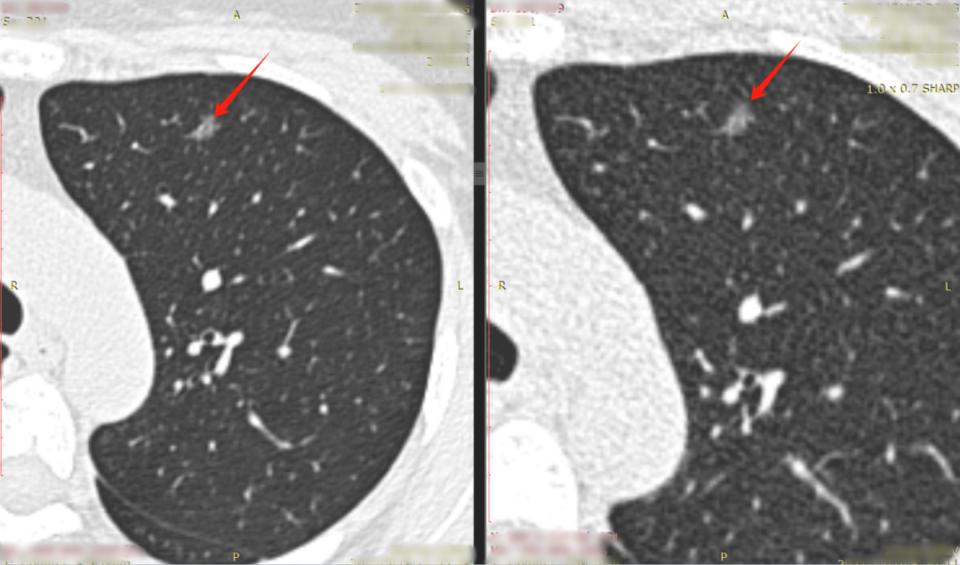

肺结节是指肺部出现的直径小于或等于3cm的圆形或类圆形病灶,虽然大多数肺结节是良性的,但部分可能是肺癌的早期表现,对肺结节的准确诊断和治疗具有重要意义,目前,随着低剂量计算机断层扫描(LDCT)的广泛应用,肺结节的检出率显著提高。

肺结节手术的适应症主要包括结节大小、生长速度、影像学特征等,术前评估则主要关注患者的一般状况、心肺功能、肿瘤标志物等方面,最新的手术标准强调,对于高风险患者,应适当放宽手术指征,对于部分小结节,可通过穿刺活检等非手术手段进行诊断与鉴别诊断。